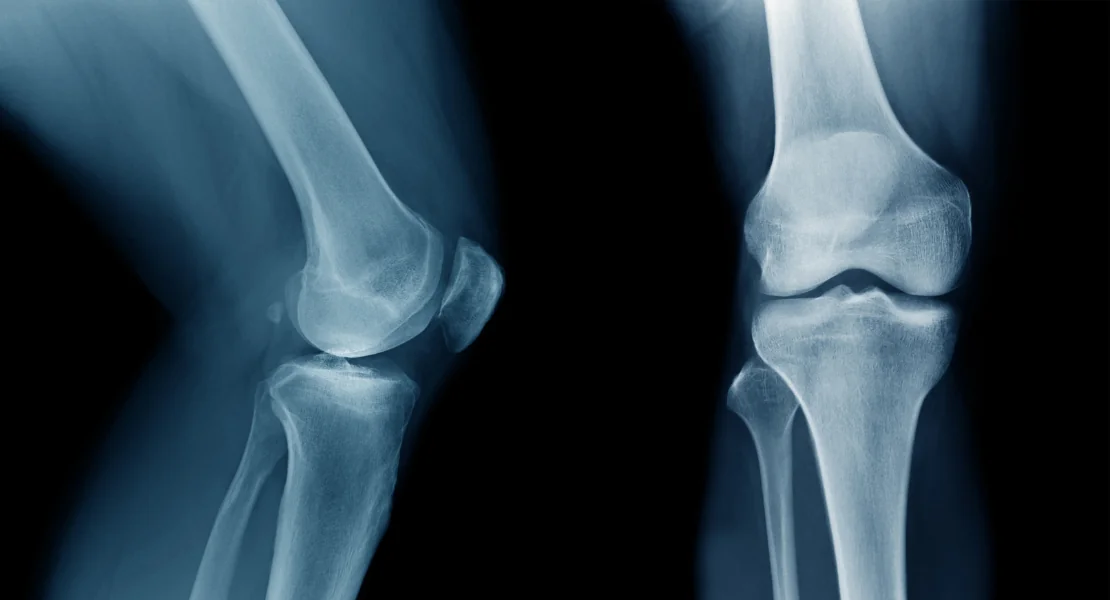

O Ligamento Cruzado Anterior, comumente chamado de LCA, é um dos ligamentos mais importantes e mais conhecidos do corpo humano.